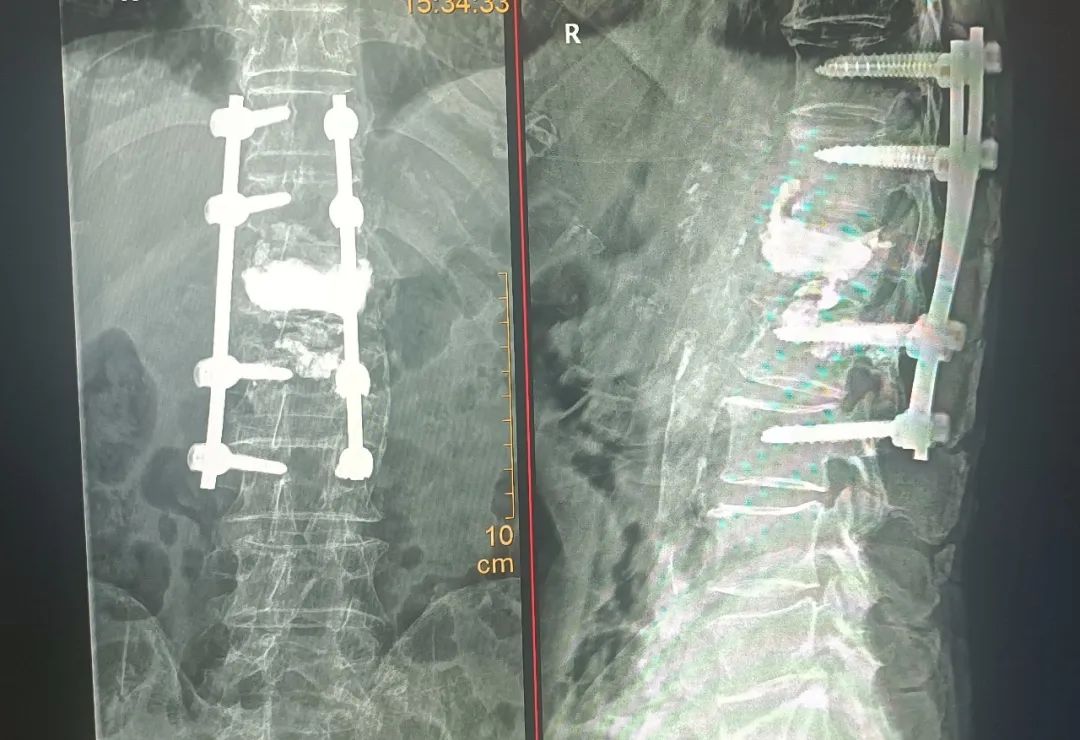

为了使张爷爷得到更舒适化的治疗,入院后,骨二科科室主任柯贤明主任医师与丁志敏副主任医师综合病史、查体及完善相关检查,组织手术团队进行详细讨论分析,在充分沟通并取得患者及家属同意后,骨二科手术团队在麻醉科的积极护航下,为患者行「全麻下胸腰椎骨折内固定+病椎椎体强化治疗」,手术过程十分顺利。

术后,患者腰背部疼痛症状完全消失,目前已经康复出院了。「谢谢医生和护士,谢谢你们!」出院时,张爷爷用慈祥的笑容表达着对医院及科室的感谢,用朴实的言语传达着心中的感恩。